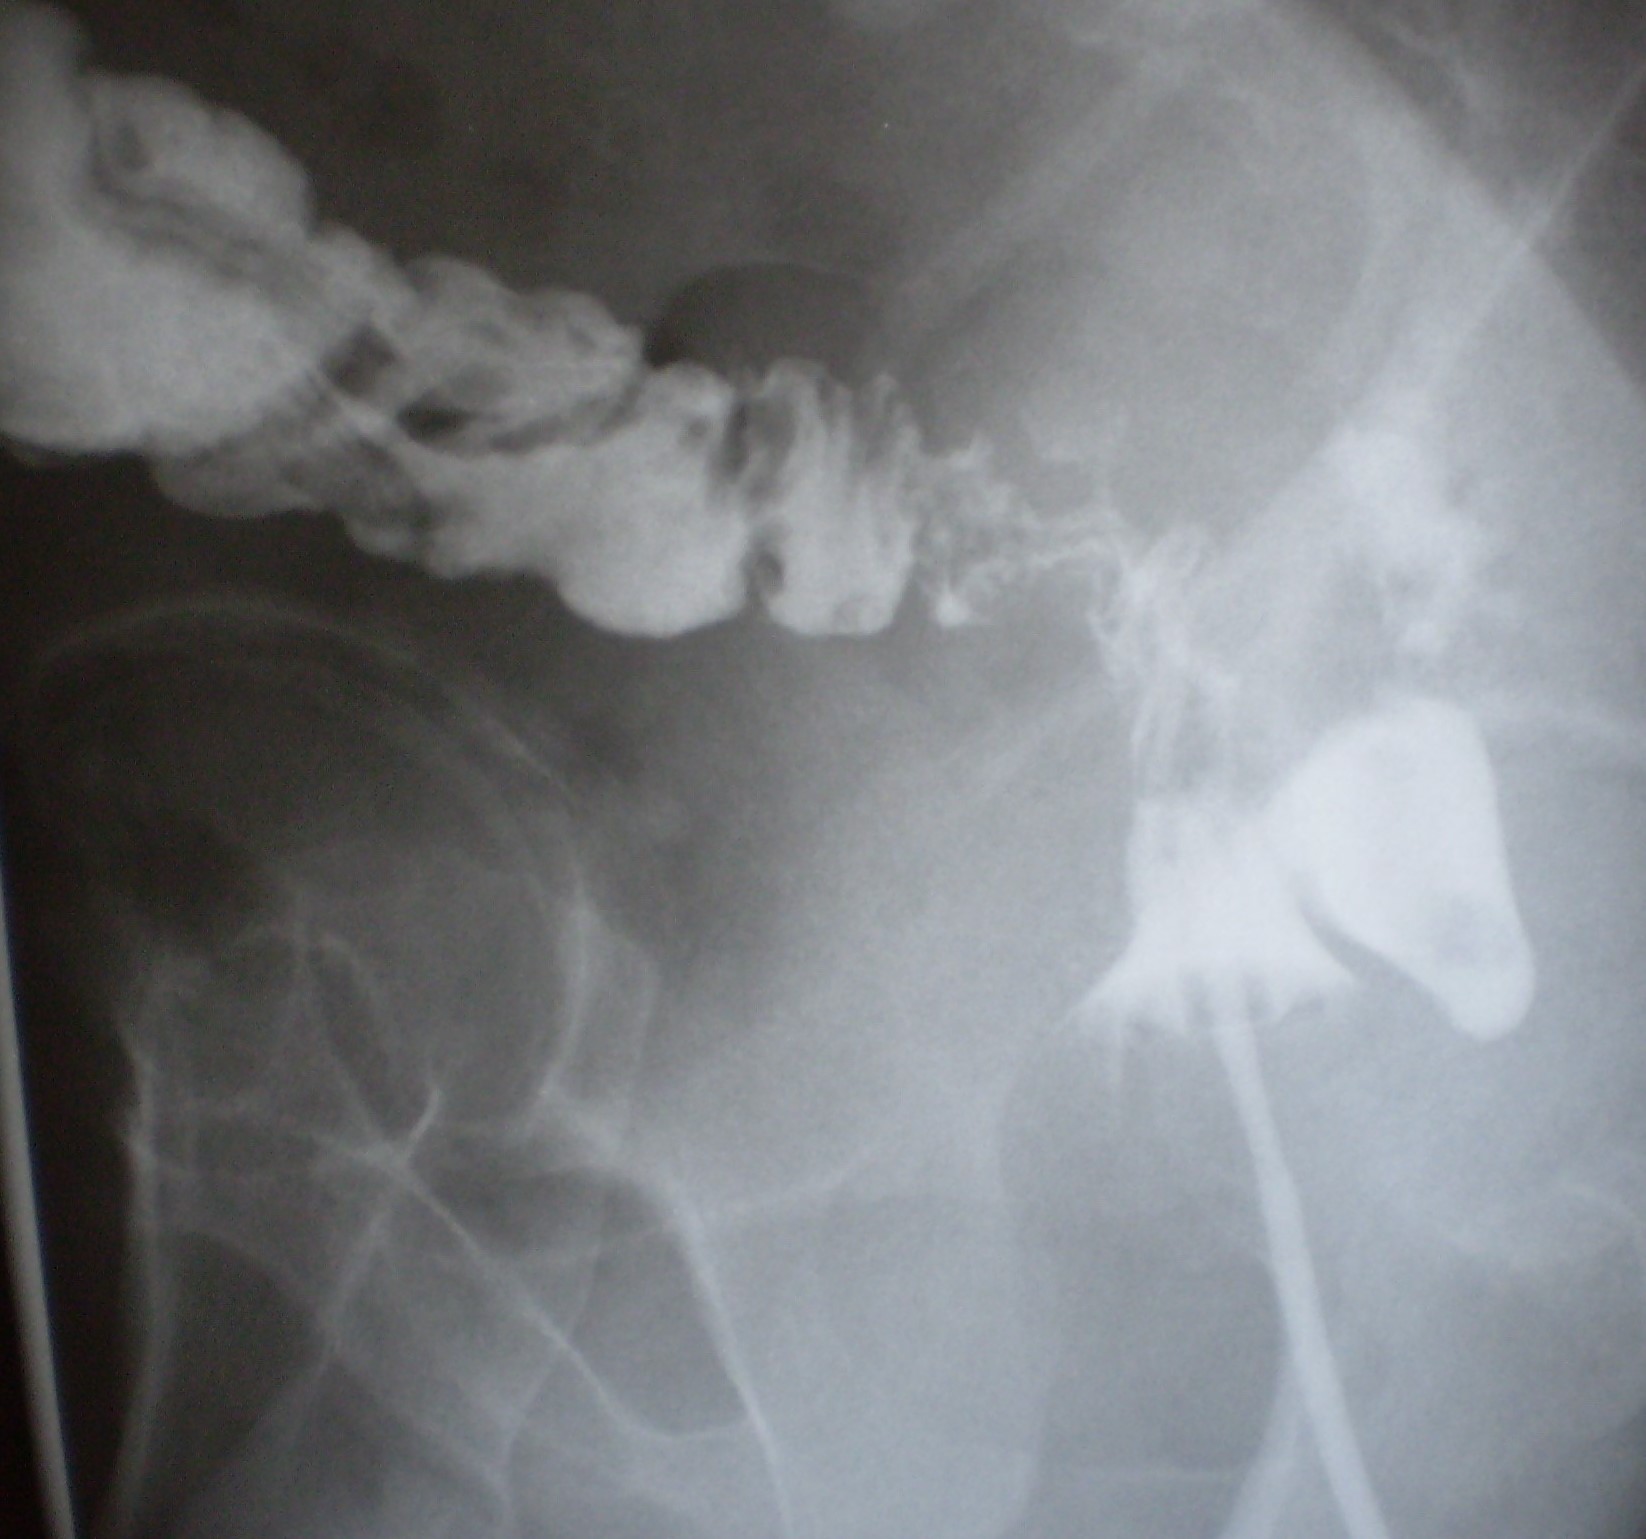

Μετεγχειρητική απεικόνιση ειλεορθικής αναστόμωσης (τροποποιημένη Duhamel). Εμφανής η αναστόμωση του τερματικού ειλεού στο πρόσθιο τοίχωμα του εναπομένοντος κολοβώματος ορθού (Ευγενική παραχώρηση Dr. V. Penopoulos)